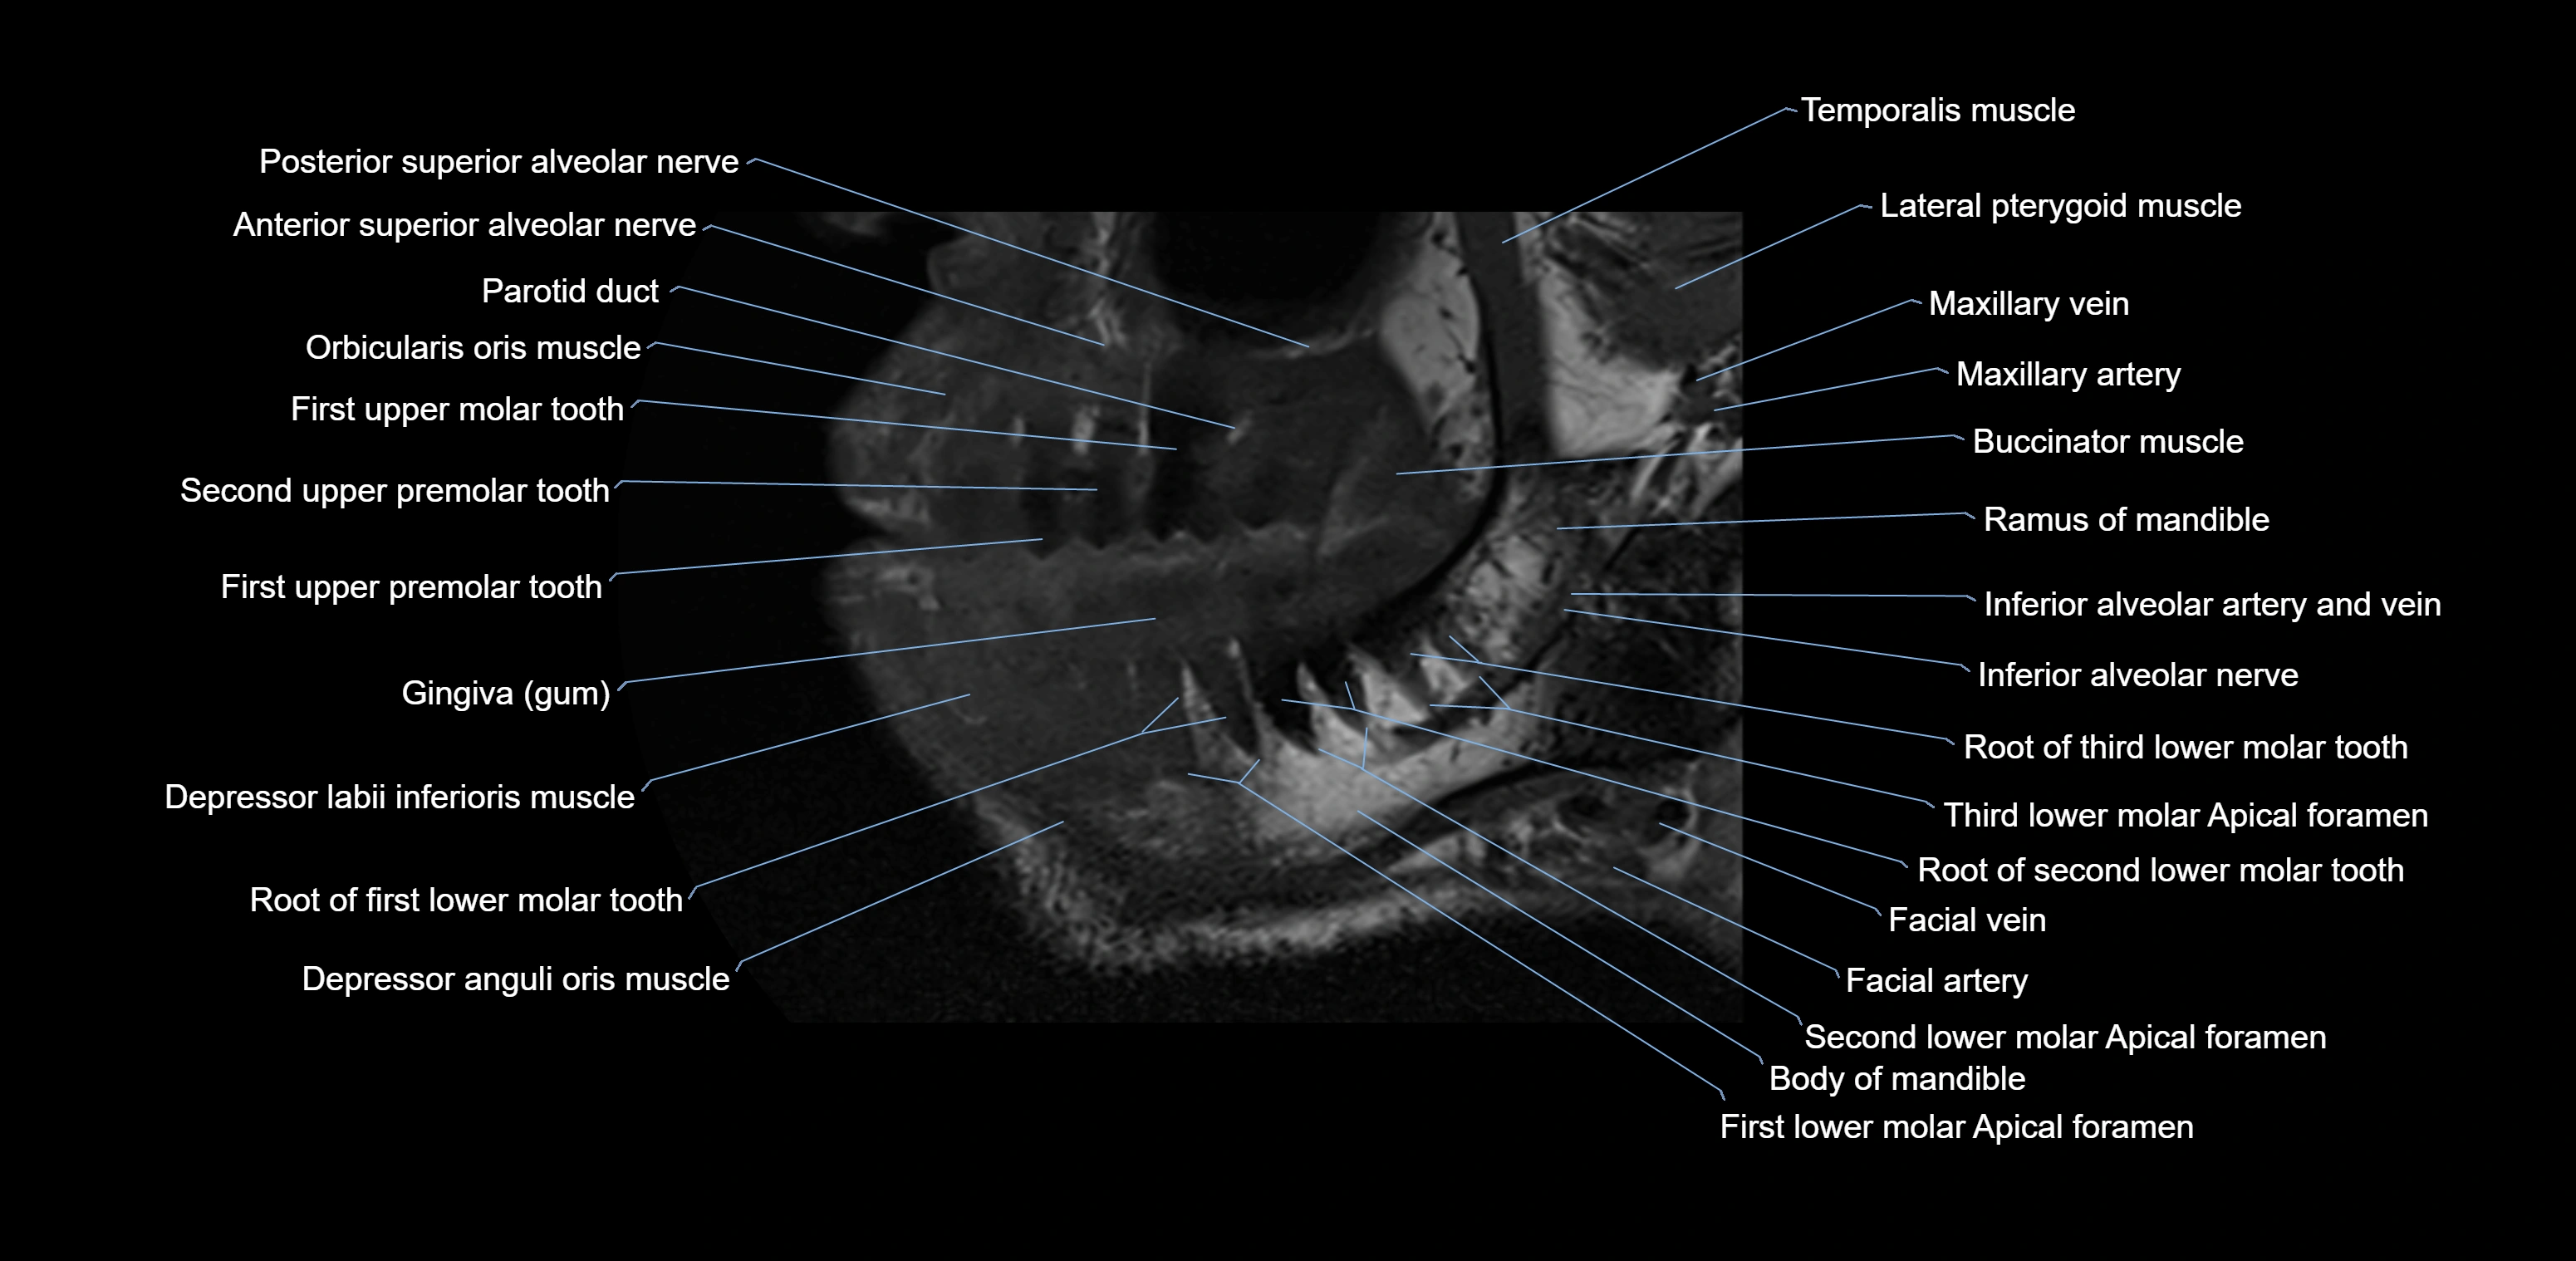

- Anterior superior alveolar nerve

- Body of mandible

- Buccinator muscle

- Depressor anguli oris muscle

- Depressor labii inferioris muscle

- Inferior alveolar nerve

- Lower molar apical foramen

- Mandibular canal

- Mandibular foramen

- Posterior superior alveolar nerve

- Ramus of mandible

- Root of lower molar tooth